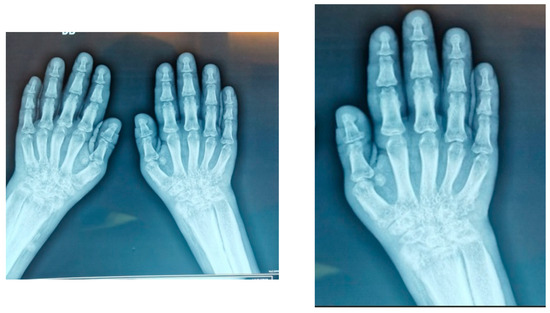

From Juvenile Idiopathic Arthritis to Pachydermoperiostosis: A Journey to an Unexpected Rare Diagnosis

Pachydermoperiostosis, also known as primary hypertrophic osteoarthropathy or Touraine–Solente–Golé syndrome, is a rare genetic disorder that represents a small fraction of hypertrophic osteoarthropathy cases. It typically begins during adolescence, affects males more frequently and follows either an autosomal dominant or recessive inheritance pattern. [...] Read more.

Pachydermoperiostosis, also known as primary hypertrophic osteoarthropathy or Touraine–Solente–Golé syndrome, is a rare genetic disorder that represents a small fraction of hypertrophic osteoarthropathy cases. It typically begins during adolescence, affects males more frequently and follows either an autosomal dominant or recessive inheritance pattern. The disease is characterized by the triad of pachydermia, periostosis and digital clubbing, often accompanied by hyperhidrosis, seborrhea, cutis verticis gyrata and joint effusions. Although articular involvement is usually non-erosive, the disorder may mimic inflammatory arthritis and lead to diagnostic delays. Recognition of the major and minor diagnostic criteria is crucial to distinguish PDP from secondary forms related to pulmonary, cardiac or neoplastic disease. Full article

(This article belongs to the Section Orthopedics)